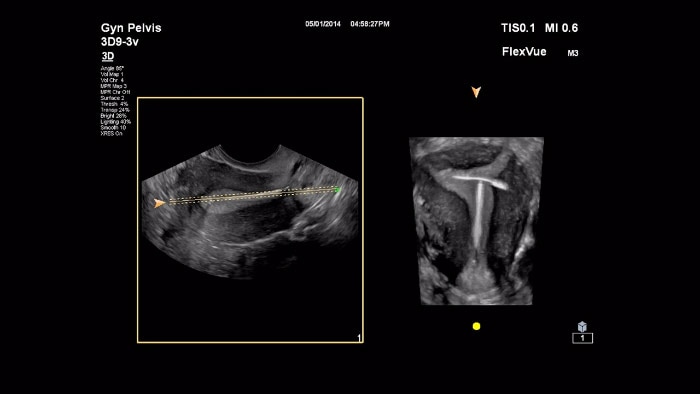

The EPIQ Elite system delivers exceptional frame rates, uniformity and penetration, with powerful features like Flow Viewer for 3D-like rendering of flow imaging data to help better visualize fetal vessels and fetal heart structures, MicroFlow Imaging High Definition (MFI-HD) to detect low-volume, low-velocity blood flow found in fetal, placental, uterine and ovarian vasculature, and TrueVue Pro 3D for photorealistic fetal images. Next Gen AutoScan reduces button pushes for greater efficiency.